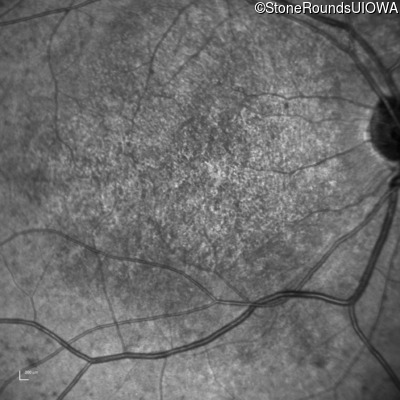

This 14 year old male began having trouble reading before the 1st grade. His parents noticed that he would not look directly at anyone.

| AR Stargardt Disease | ABCA4 | Ala1038Val GCC>GTC / Leu541Pro CTA>CCA | IVS36+3 del4tAAGT | AR |